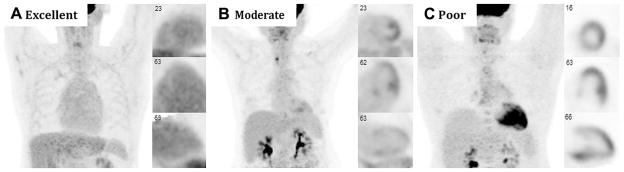

Figure 2.

Cardiac 18F-FDG PET imaging demonstrating variable suppression in three patients without cardiac disease: A excellent myocardial suppression with blood pool activity that exceeds that of the myocardium, B moderate myocardial suppression with diffuse low-level myocardial 18F-FDG uptake and non-specific focally increased uptake in the papillary muscles and lateral wall, and C poor myocardial suppression with diffuse 18F-FDG uptake throughout the heart.